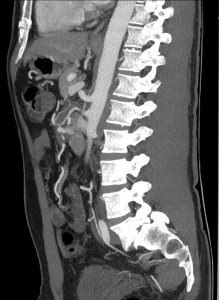

- Las imágenes sagitales son útiles para evaluar el origen de las arterias mesentéricas y sus variaciones.

Se realiza TC de abdomen en vacío y con contraste en fase portal:

Estamos ante un cuadro de isquemia intestinal en un paciente con bajo gasto cardiaco con afectación principal de asas intestino delgado, territorio vacularizado por la arteria mesentérica superior.